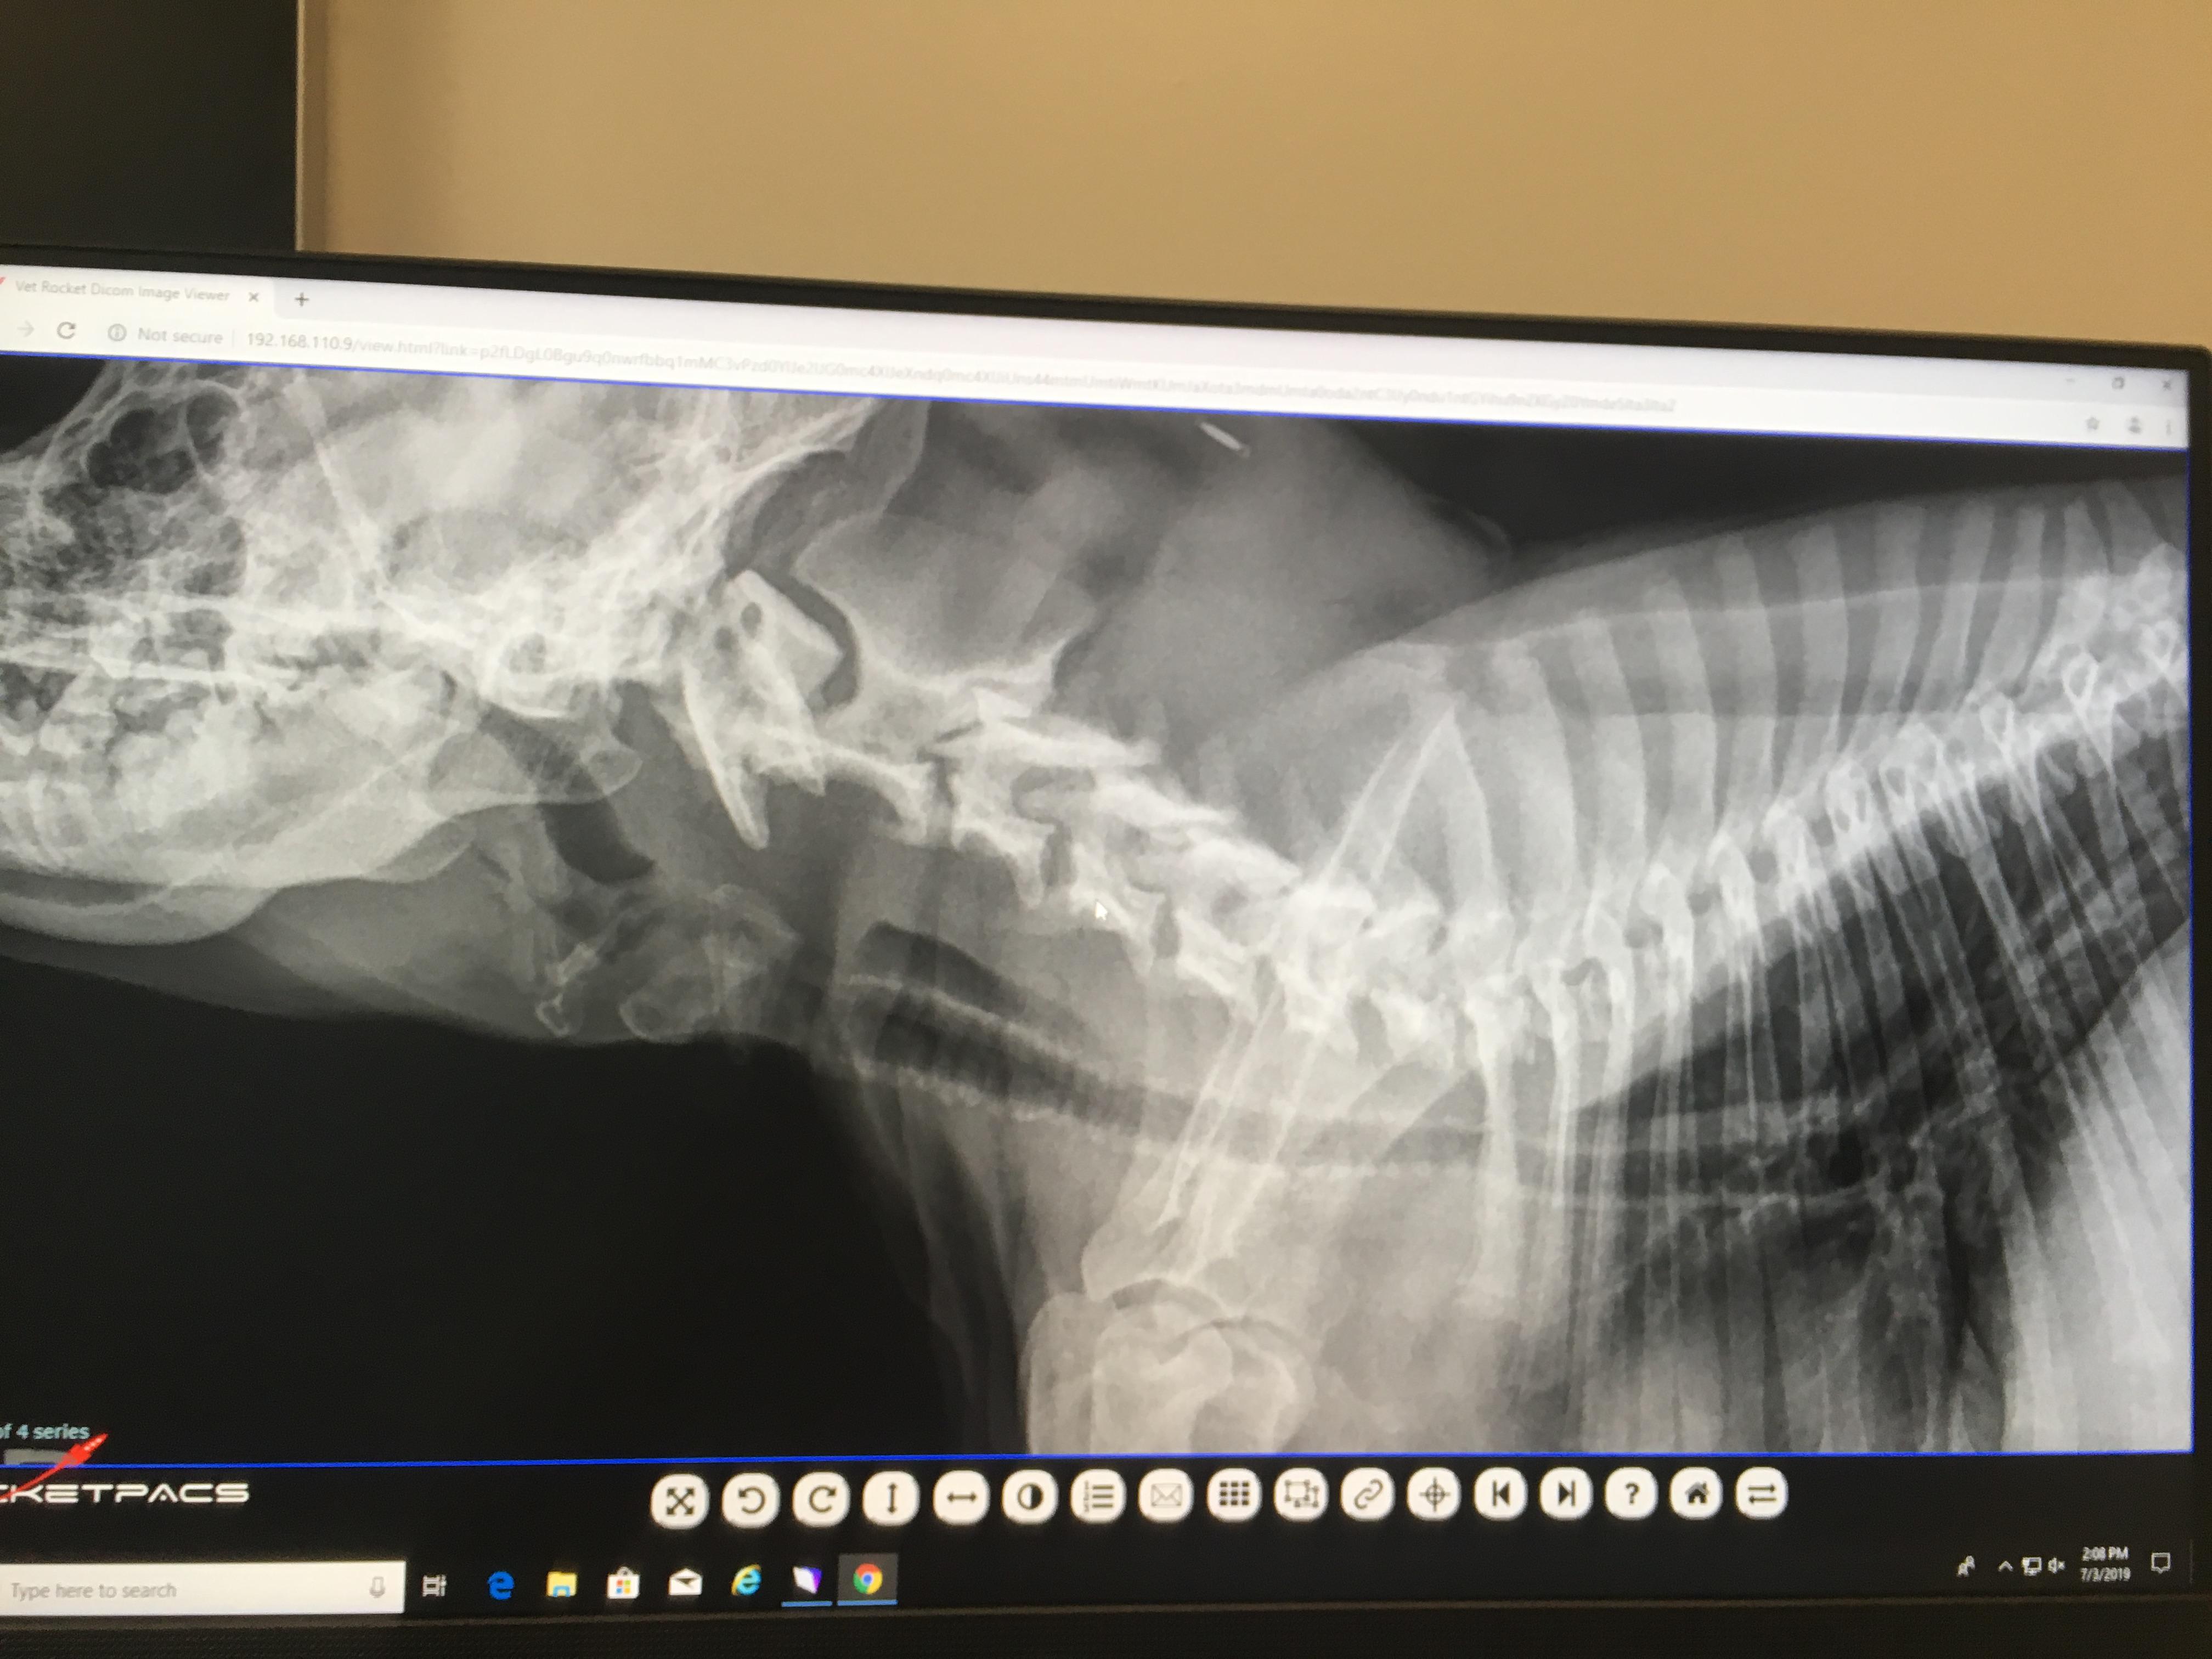

I have a 1 y/o american bully (pocket). We have had him since he was 8 wks old. Always has had labored breathing, but just attributed it to his short snout. Recently took him to a specialist due to his labored breathing appears to be getting worse. X-rays revealed tracheal narrowing with mineralizations. They said his tracheal flaps aren’t moving in their own and they want to permanently suture one flap open. Is this a common surgery? Also what could be the cause of this mineralization?

Yes, this is a pretty common surgery called a "tie back". I suggest you have it done if the specialist has recommended it. The mineralization is nothing to be concerned about - it is a very common finding although usually in older dogs. No one is quite sure why the body deposits the minerals in the tissue although it is suspected to be due to inflammation.